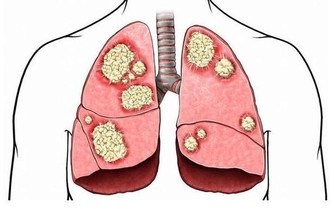

不讓「胃病變胃癌」!一定要這樣吃,晚知道後悔一輩子!趕快改過來!!

下班回家後到了七八點才好好的吃一頓晚飯,而與之類似的一系列壞習慣使胃癌患者越來越多。

去了醫院做了檢查才直到出現了胃部病變,需要手術,如果再晚些治療可能會發展成胃癌……